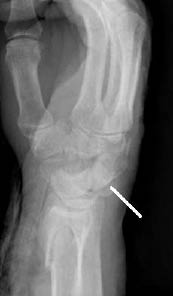

Figure 10: Colles' Fracture

Lateral radiograph of a Colles' fracture. Note the "dinner fork" deformity.

Patients with this type of injury often present with a characteristic "dinner fork" deformity, where the wrist is held is dorsiflexion.1,3 (See Figure 10.) These fractures may be open or closed, with patients complaining of swelling and pain over the dorsum of the wrist. Often patients complain of paresthesias in the median nerve distribution secondary to compression of the nerve by the fracture fragments or an expanding hematoma.